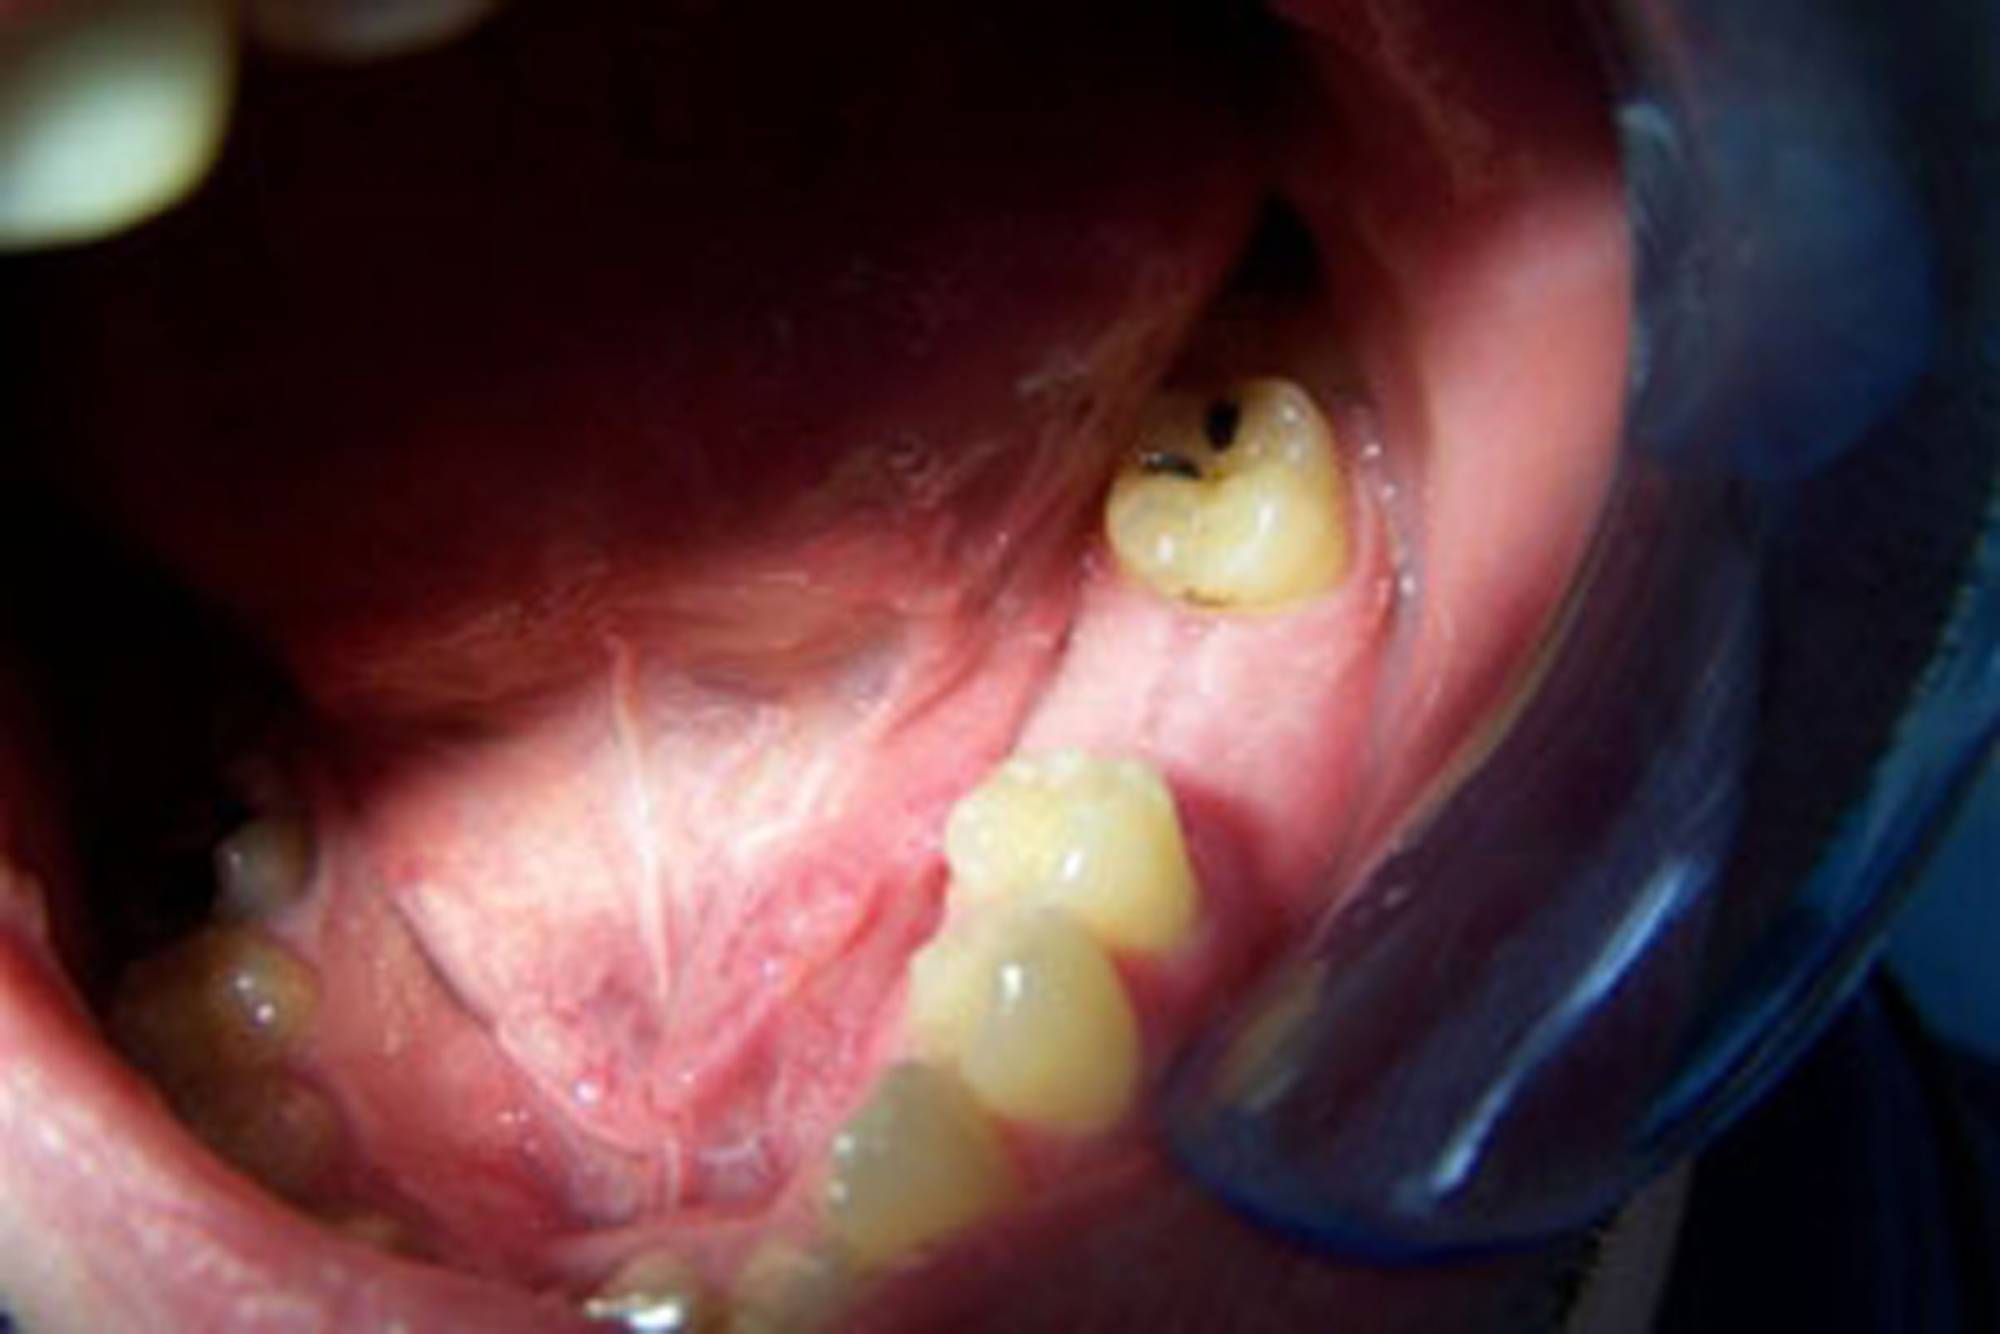

Generalmente devono trascorrere alcuni mesi tra l’intervento chirurgico di inserimento di un impianto e la realizzazione della protesi da fissare ad esso.

In questo lasso di tempo, nel quale l'impianto è sommerso sotto la gengiva e si avvia il processo di guarigione ossea, si realizza l'osteointegrazione, ovvero un intimo contatto fra l’osso e la superficie biocompatibile in titanio dell’impianto.

Tuttavia, in alcuni casi selezionati, è possibile protesizzare gli impianti subito dopo il loro posizionamento, nel giro di pochi giorni o addirittura nel corso della stessa seduta: questa tecnica è definita “carico immediato” e consente al paziente di entrare in Studio con la sua vecchia dentiera e di uscire il giorno stesso con una protesi fissa.